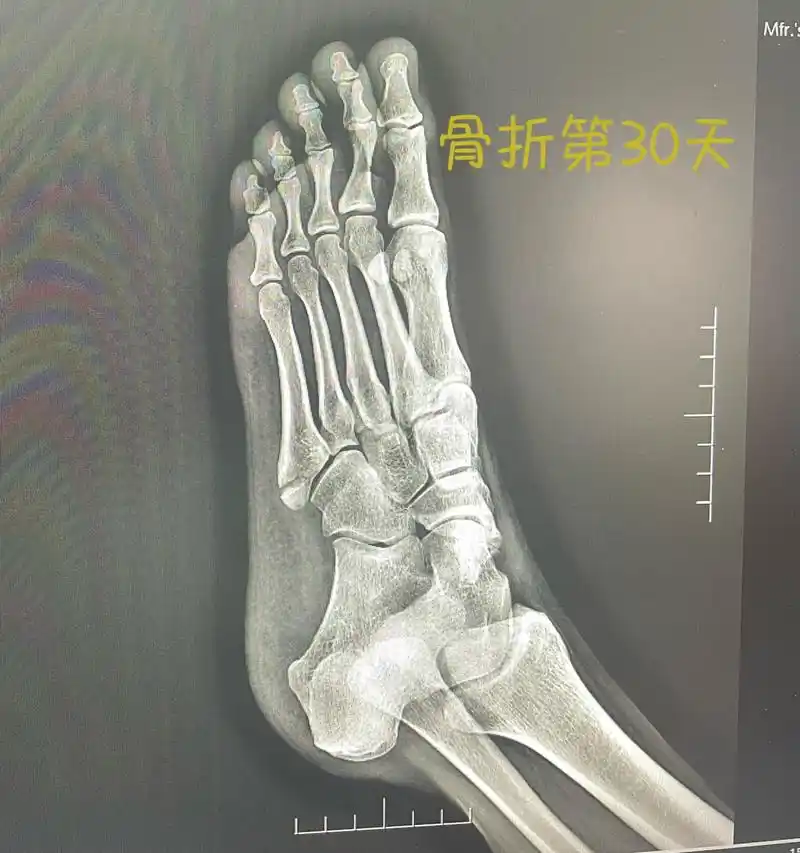

小武日记之第一例第五跖骨基底部骨折

第五跖骨骨折1个月 从2月13到3.14,骨折30天了,满一个月了.